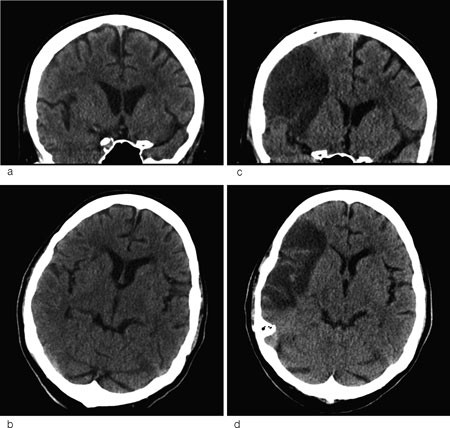

En risiko ved trombolytisk behandling er hemoragisk transformasjon av hjerneinfarktet. Småblødninger (hemoragisk infarkt) er vanligvis tegn på vellykket rekanalisering og er assosiert med godt langtidsresultat (20). Større blødninger (parenkymatøst hematom) er vanligvis assosiert med klinisk forverring og dårlig langtidsresultat og opptrer hos 5 – 7 % av behandlede pasienter. Den beste måten å unngå blødningskomplikasjoner på er å følge behandlingsprotokollen nøye.

Hemoragisk transformasjon. Hemoragisk transformasjon av et primært iskemisk infarktområde opptrer spontant hos rundt 5 % av pasientene med hjerneinfarkt, og er blitt et hyppigere fenomen etter innføringen av intravenøs trombolyse. Behandling av symptomatisk hemoragisk transformasjon (hematom) følger retningslinjene for spontane hjerneblødninger.